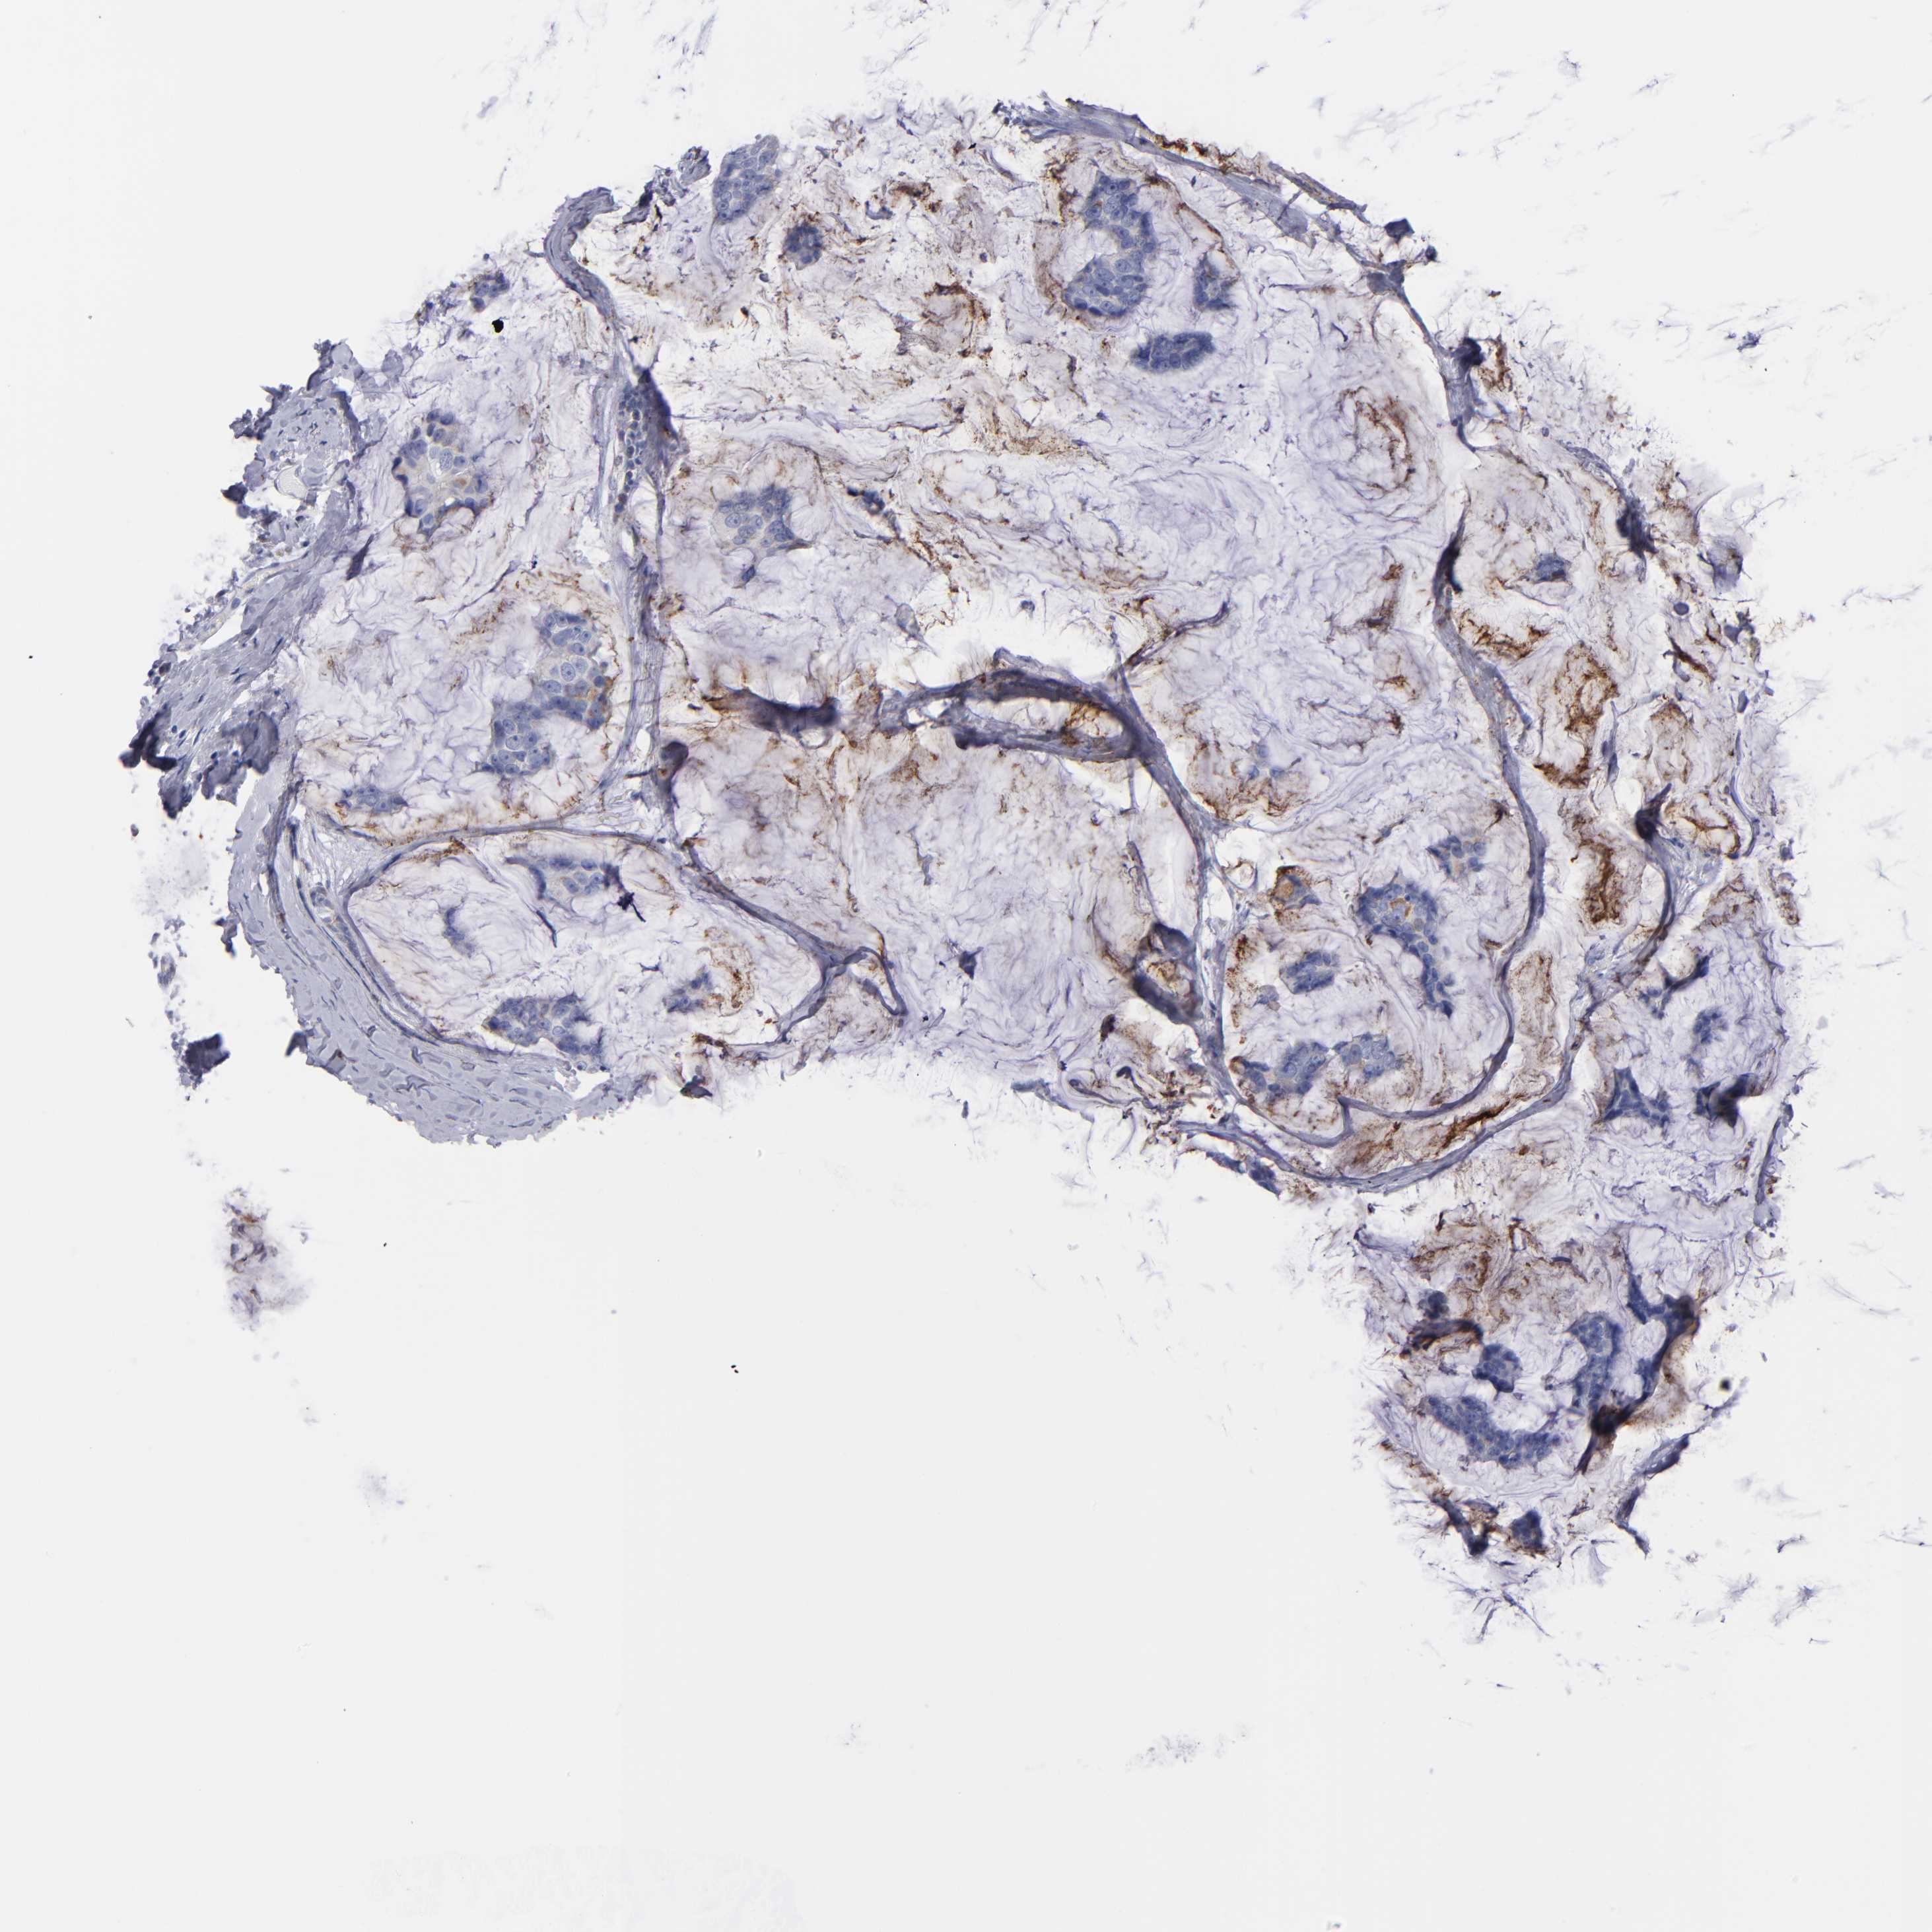

CANCER BREAST CANCER Show tissue menu

BRCA TCGA BRCA VALIDATION PROTEIN EXPRESSION